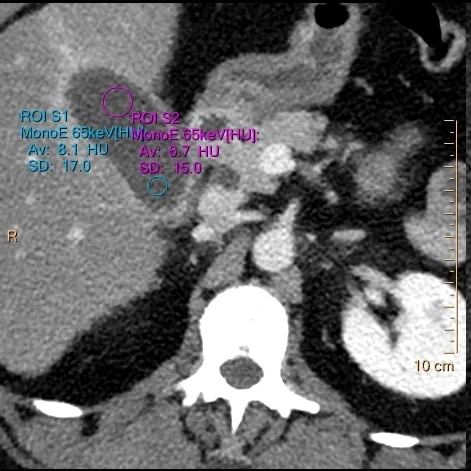

ROI placed over expected location of gallstone (blue) and bile (magenta) on convantional CT show nearly identical density (8.1 vs 6.7 HU)